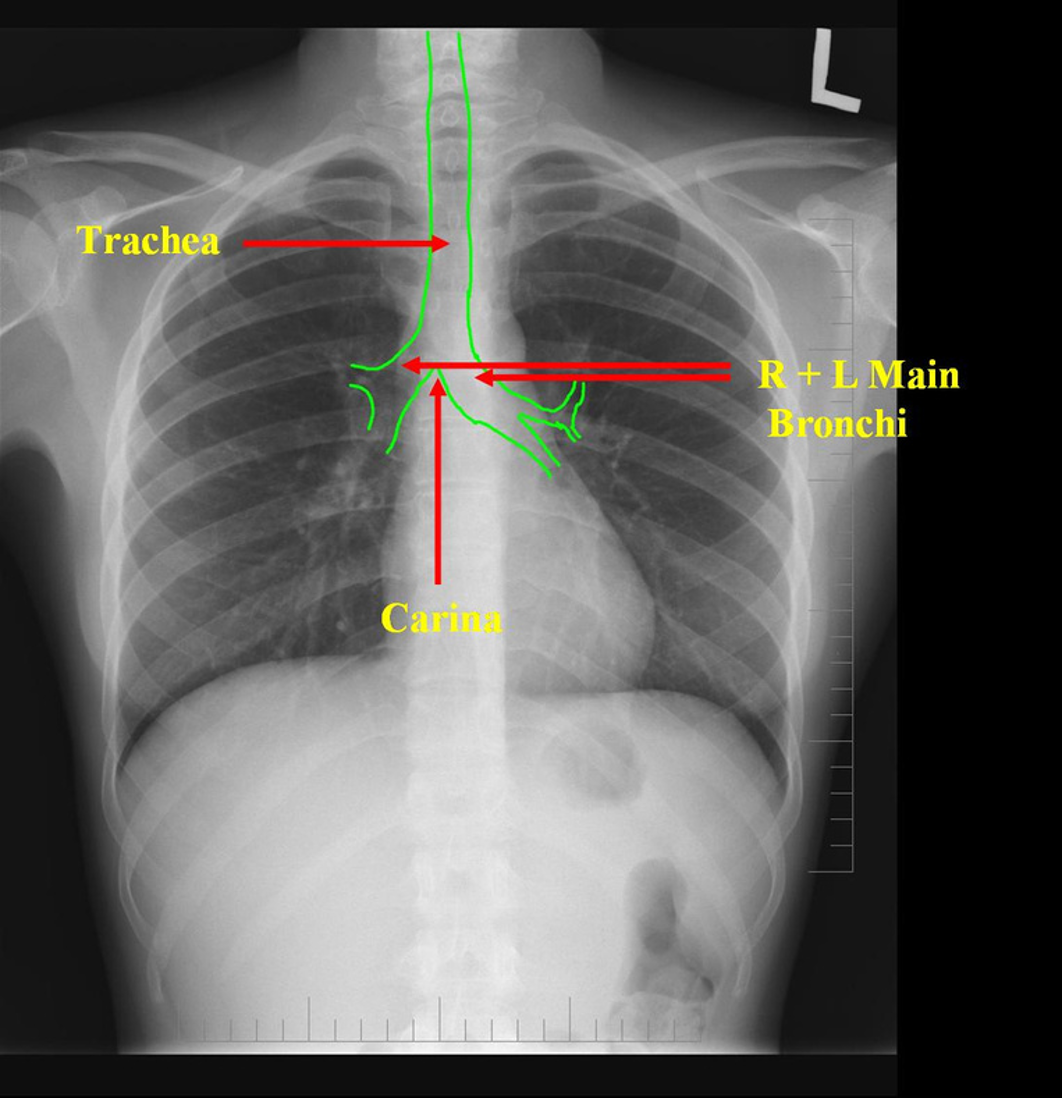

Airway (trachea, carina, bronchi, hilar structures)

Carina

NOTE: a correctly placed NG tube will bisect the carina

The ____ main bronchus is wider, shorter and more vertical than the ____ main bronchus.

right; left

It is more common for inhaled foreign objects to become lodged in the ____ main bronchus.

right

On CXR, the ___ hila should appear lower than the ___ hila

right hila appears lower than the left

Airway Structures on CXR